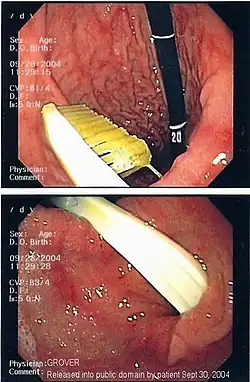

| An endoscopy image of the stomach, showing a foreign body in the form of a swallowed toothbrush. | |

One of the most common locations for a foreign body is the alimentary tract.

It is possible for foreign bodies to enter the tract from the mouth or rectum.